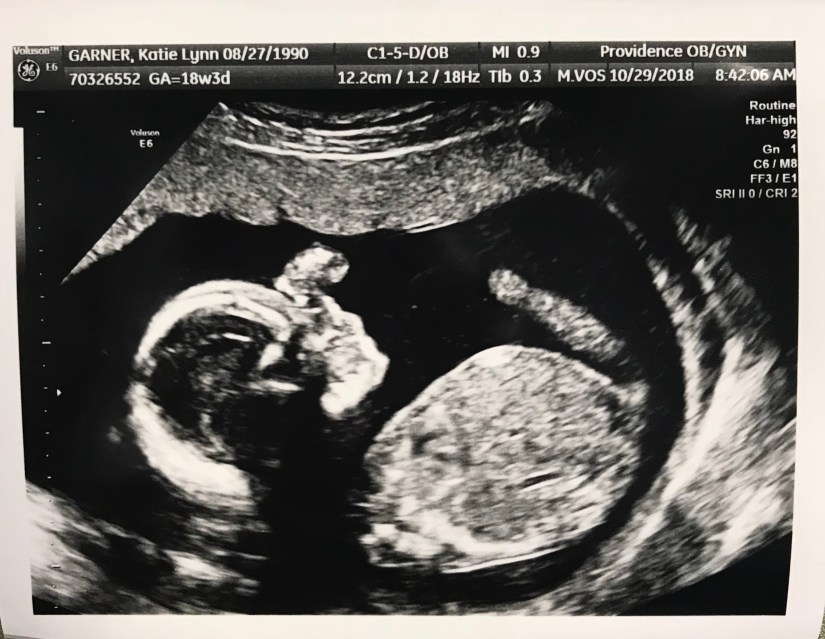

We had our last ultrasound two weeks back at the anatomy scan and now we’re officially stuck with not knowing the gender! Only the tech. checked the gender, it won’t be on my chart, and my own doctor doesn’t even know so theres no option for slip ups! I’m sooo excited!!